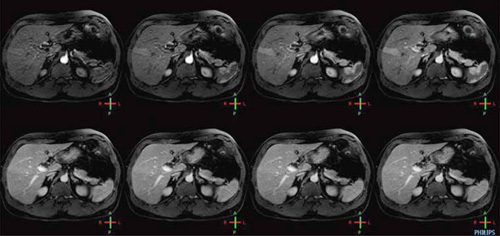

大特価 チラシ 腹部のMRI Amazon | 通販 | |本 力 荒木 | 第3版 医学一般